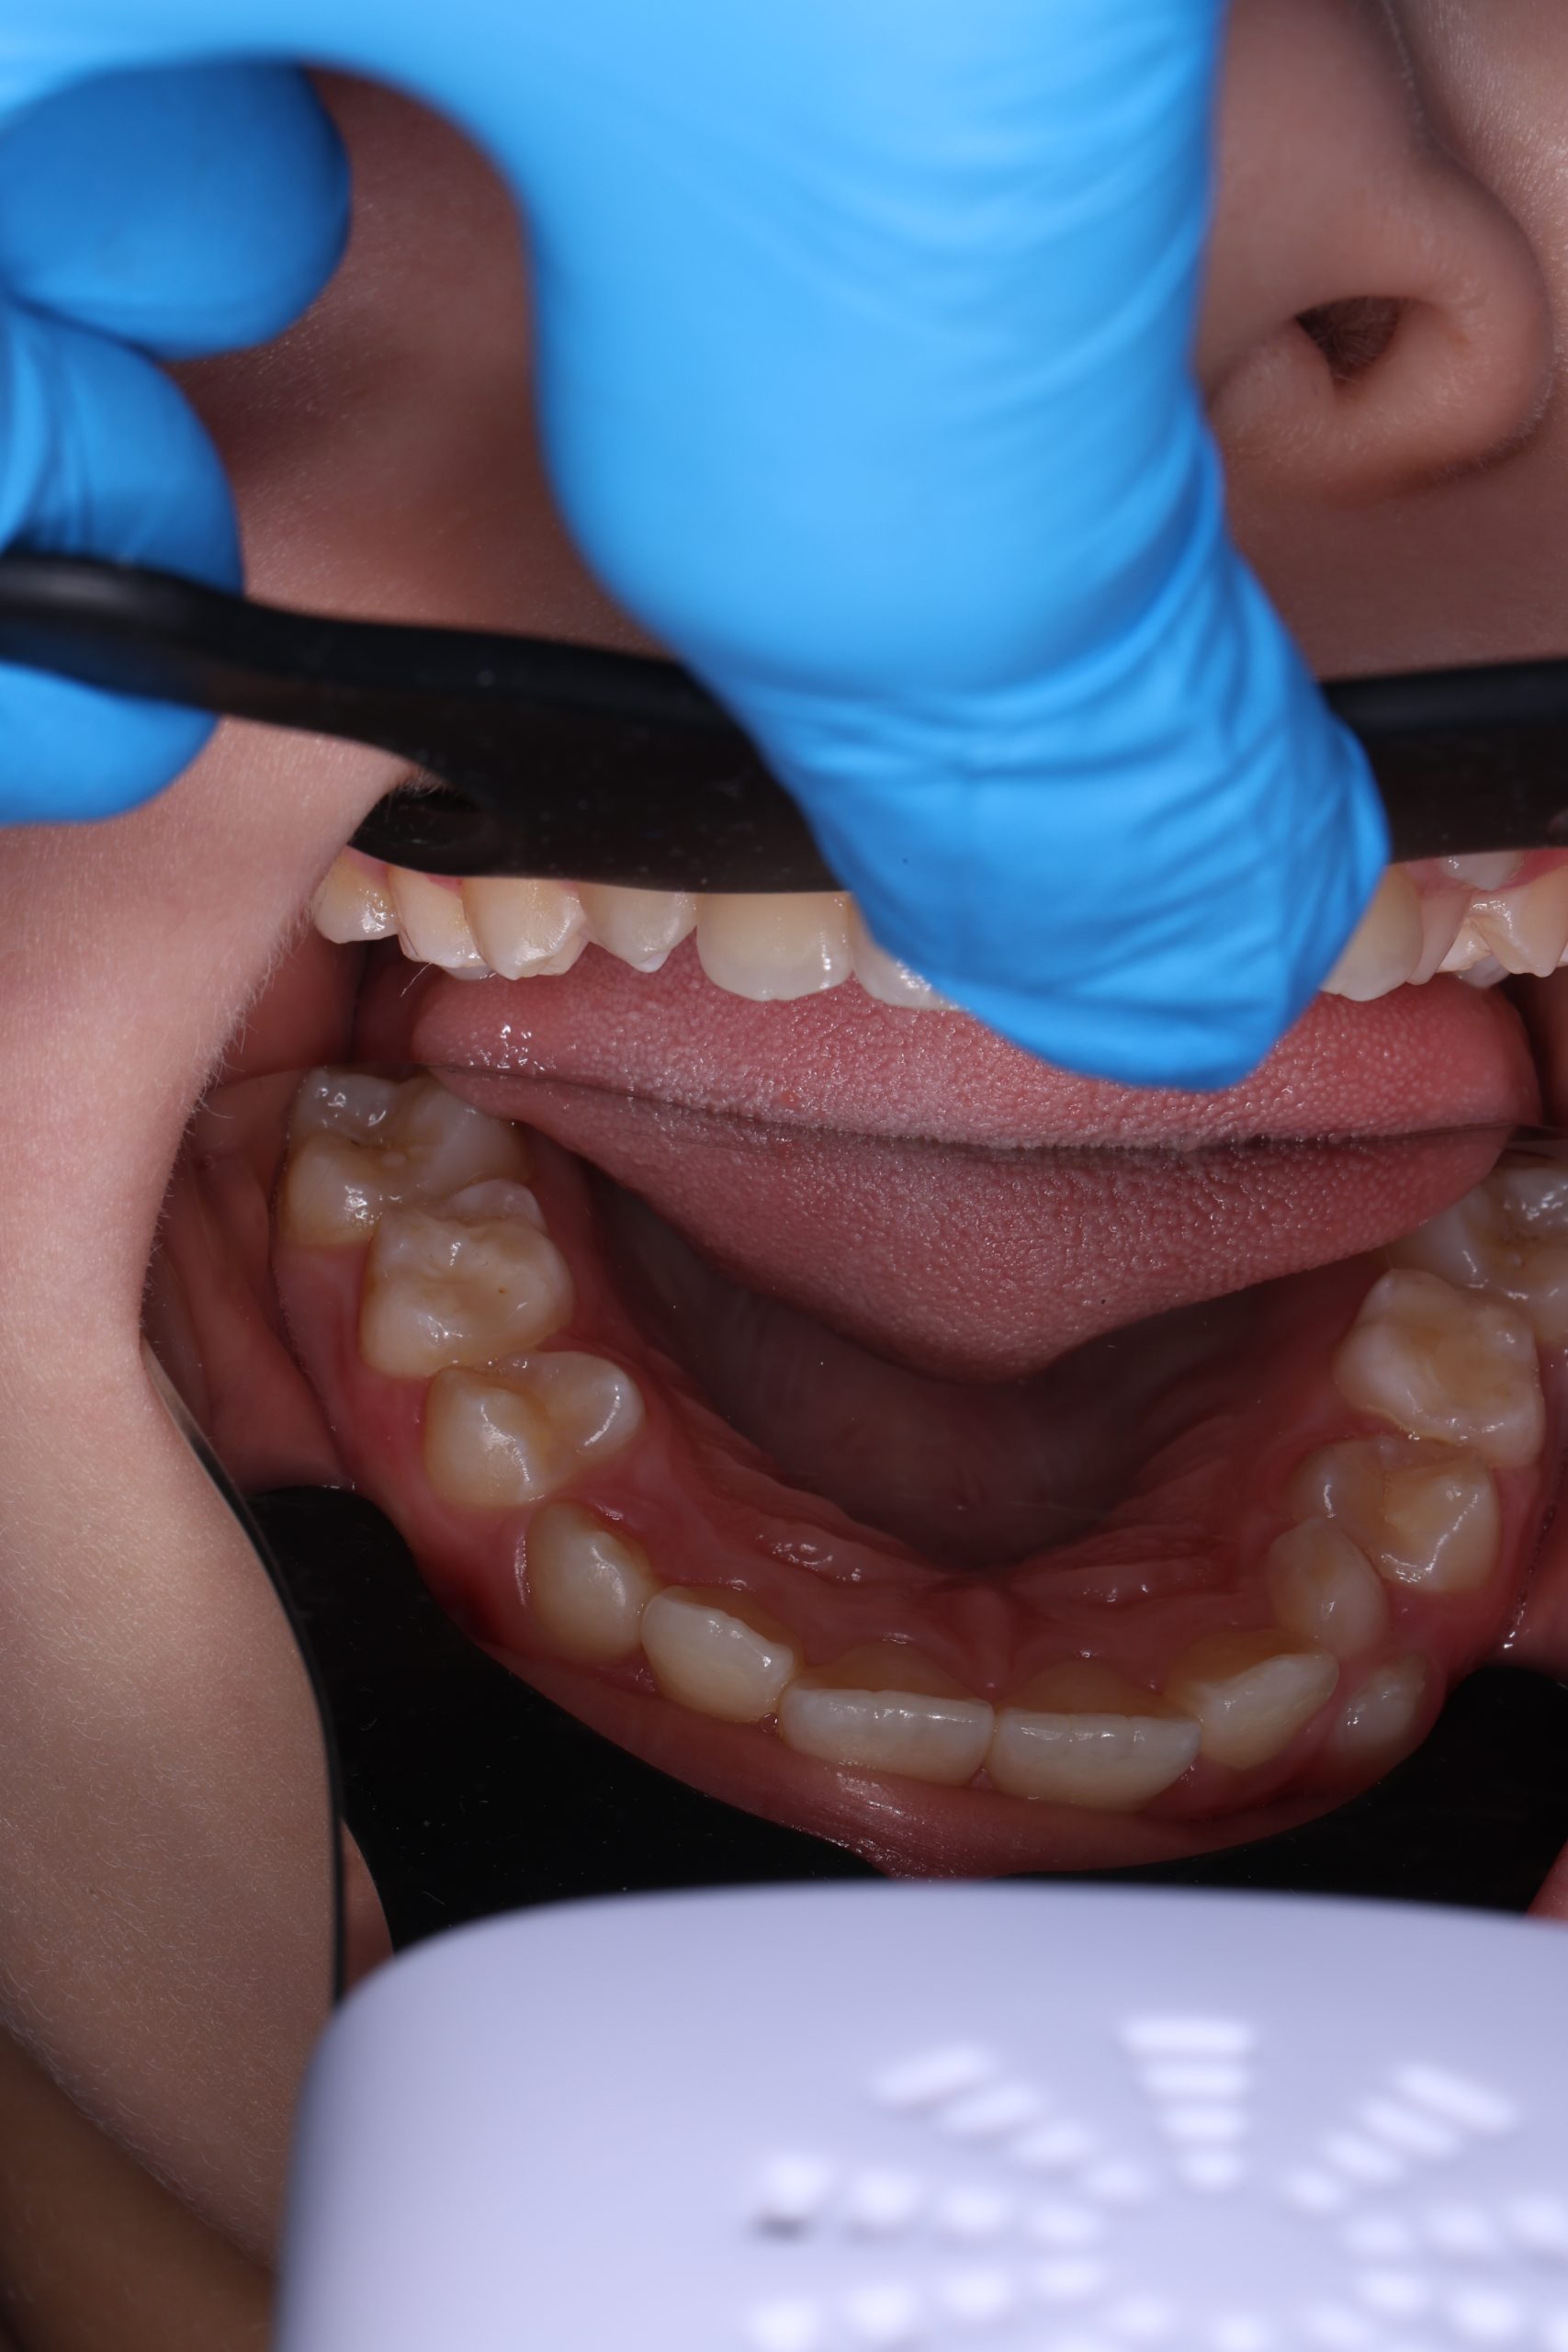

We examine the condition of teeth, gums, and bite. - Plaque Disclosure with Special Indicators

Areas that weren’t cleaned well appear purple. The darker the shade, the older the plaque. This helps both kids and parents understand where brushing needs to improve. - Brushing Training & Home Care Tools Selection